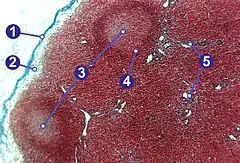

Each lymph node is surrounded by a fibrous capsule, which extends inside a lymph node to form trabeculae.[3] The substance of a lymph node is divided into the outer cortex and the inner medulla.[3] These are rich with cells.[4] The hilum is an indent on the concave surface of the lymph node where lymphatic vessels leave and blood vessels enter and leave.[4]

A lymph node is divided into compartments called nodules (or lobules), each consisting of a region of cortex with combined follicle B cells, a paracortex of T cells, and a part of the nodule in the medulla.[15] The substance of a lymph node is divided into the outer cortex and the inner medulla.[3] The cortex of a lymph node is the outer portion of the node, underneath the capsule and the subcapsular sinus.[15] It has an outer part and a deeper part known as the paracortex.[15] The outer cortex consists of groups of mainly inactivated B cells called follicles.[4] When activated, these may develop into what is called a germinal centre.[4] The deeper paracortex mainly consists of the T cells.[4] Here the T-cells mainly interact with dendritic cells, and the reticular network is dense.[16]

The medulla contains large blood vessels, sinuses and medullary cords that contain antibody-secreting plasma cells. There are fewer cells in the medulla.[4]

The medullary cords are cords of lymphatic tissue, and include plasma cells, macrophages, and B cells.

In the lymphatic system a lymph node is a secondary lymphoid organ.[4] Lymph nodes contain lymphocytes, a type of white blood cell, and are primarily made up of B cells and T cells.[4] B cells are mainly found in the outer cortex where they are clustered together as follicular B cells in lymphoid follicles, and T cells and dendritic cells are mainly found in the paracortex.[17]

There are fewer cells in the medulla than the cortex.[4] The medulla contains plasma cells, as well as macrophages which are present within the medullary sinuses.[17]